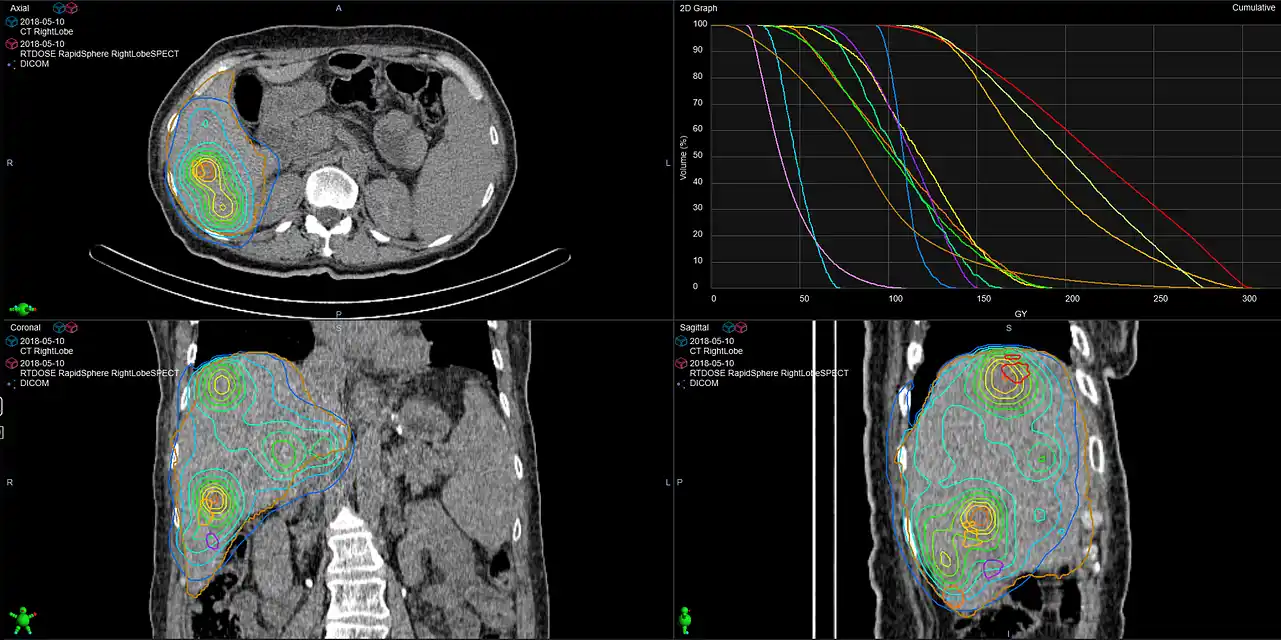

Voxel Based Dosimetry

Convert activity concentration from a post-treatment emission tomography to a 3D dose

RapidSphere provides software tools for liver, lung, and tumor segmentation, multi-modality deformable image registration, and post-treatment dosimetry for Y90 radioembolization on PET and SPECT images.